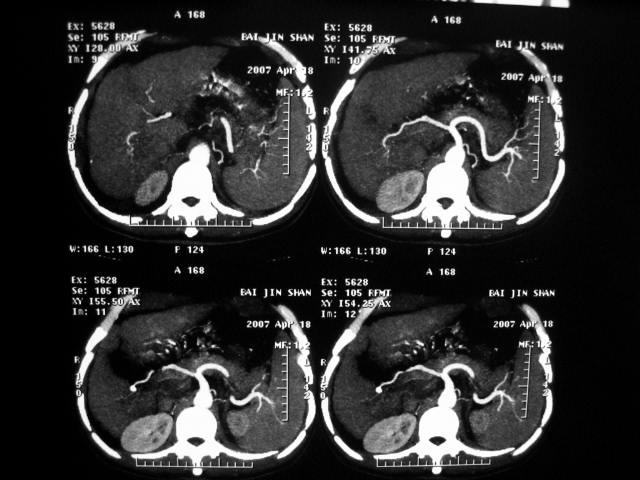

标题: CT7751:病人,50岁,肝硬化多年,行CT三期扫描 [打印本页]

标题: CT7751:病人,50岁,肝硬化多年,行CT三期扫描

动脉期病灶见轻度强化,考虑肝癌可能性大。

增强扫描所传图像不全面,应传各期图像,单传动脉期不能完全说明问题。

动脉期轻度强化 考虑 肝右叶小肝癌可能性大

肝硬化 脾大 胃底静脉曲张 肝癌 门腔间淋巴结肿大

肝硬化、脾大,静脉曲张,肝右叶低密度灶,增强无明显强化,还是考虑肝癌可能性大,建议结合afp检查。

肝癌分为肝细胞性和胆管细胞性,从强化表现来看,确切地说应是胆管细胞癌.